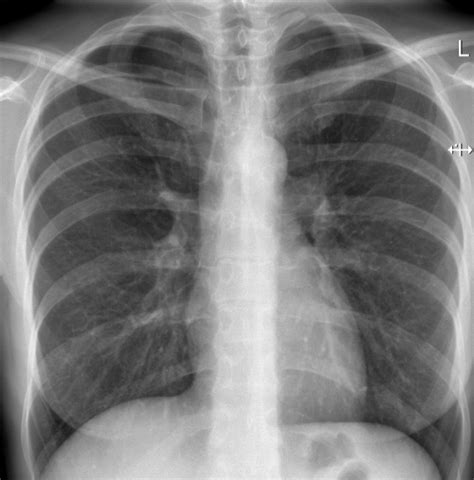

Bronchiolitida je nakažlivá virová infekce. Lékař diagnostikuje bronchiolitidu pozorováním svého dítěte a posloucháním zvuků jeho dechu stetoskopem. V těžkých případech bronchiolitidy může lékař nařídit laboratorní vyšetření a rentgen.

- Rentgen hrudníku.

Syndrom dechové tísně novorozence (RDS)

Syndrom dechové tísně novorozence (RDS - Respiratory Distress Syndrome, syndrom hyalinních membrán, idiopatický RDS) je způsoben anatomickou a funkční nezralostí plic - nedostatkem surfaktantu. Postihuje téměř výlučně nezralé novorozence.

Klinicky se manifestuje ihned po narození jako rychle progredující respirační insuficience. Incidence a závažnost RDS je nepřímo úměrná gestačnímu stáří novorozence.

Patofyziologie RDS

U dětí s RDS, které nejsou léčené podáním surfaktantu, dochází již půl hodiny po narození k nekróze epiteliálních buněk alveolů. Epiteliální buňky se odlupují od bazální membrány a vytváří shluky hyalinních membrán. Současně dochází k difuznímu intersticiálnímu edému. Lymfatické cévy jsou dilatované v důsledku opožděného vstřebávání tekutiny v plicích.

Během 24 hodin dochází ke extenzivní generalizované tvorbě membrán, které se hromadí především v terminálních a respiračních bronchiolech, a to zejména v místě větvení dýchacích cest. Alveoly jsou zkolabované a těmito membránami vystlané nejsou. Hyalinní membrány jsou tvořené debris z odumřelých pneumocytů, koagulovanými plazmatickými proteiny, které se uvolnily z poškozených kapilár, a exsudovaným fibrinem.

Po 24 hodinách se začnou v lumen dýchacích cest objevovat první makrofágy, které v průběhu následujících 2 - 3 dnů pohlcují membrány. Po 48 hodinách se začíná obnovovat epitel a na povrchu alveolů se začíná objevovat surfaktant. Při nekomplikovaném průběhu RDS mizí hyalinní membrány do 7. dne života.